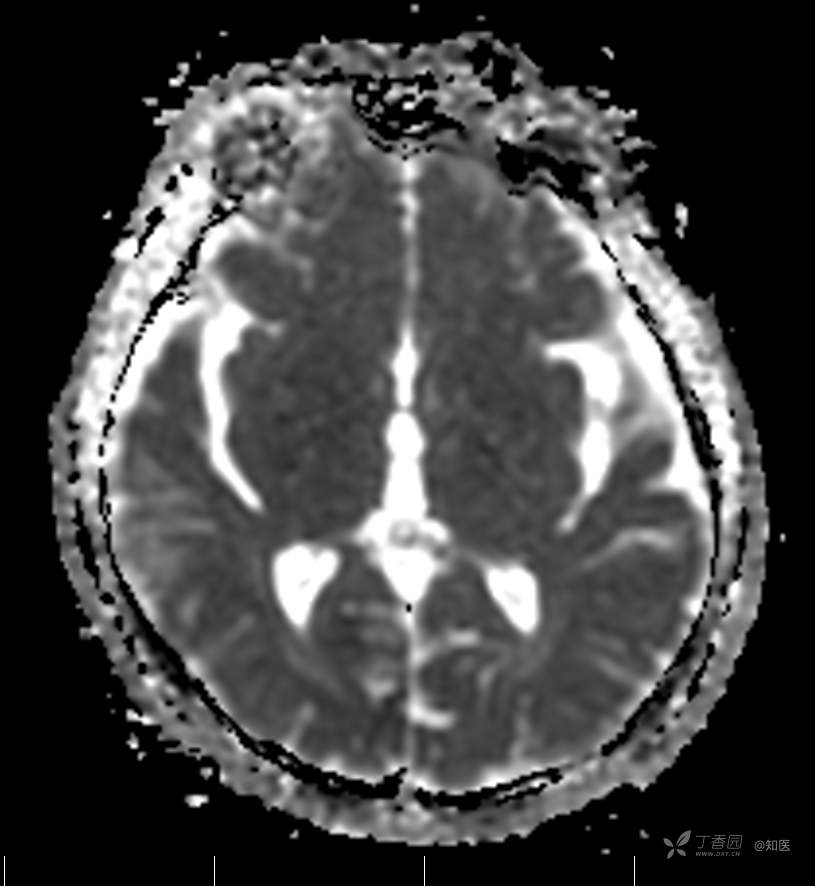

2021-6-15 ADC

2021-06-16日晨查房,患者自觉入院治疗后肢体无力症状较前稍改善,仍有活动后气短,余未诉特殊不适。ALSFRS-R评分:44分(单项均大于等于2分)。血压:123/63mmHg。神经系统查体:GCS 15分,右利手,查体合作,问答切题,粗测智能基本正常。额纹对称,双眼闭目紧,双侧瞳孔等大等圆,直径约3.0mm,对光反射灵敏,眼球运动自如,无眼震,双侧鼻唇沟对称等深,口角无歪斜。悬雍垂居中,双侧软腭抬举良好,咽反射灵敏、转颈、耸肩均一致有力。颈屈肌、颈伸肌力量5级。伸舌居中,无舌肌纤颤及萎缩。双侧岗上肌、岗下肌可见萎缩;双侧三角肌可见偶发肉跳、肌力5级,左侧肱二头肌肌力4+级、右侧4-级,双侧肱三头肌肌力4+级;双手握力可,双手大小鱼际肌及第一骨间肌可见萎缩,左侧明显,左侧手腕背伸力量4级、右侧4+级,双侧拇短展肌肌力4-级,双侧示指伸肌肌力3级,左侧指总伸肌肌力4级、右侧4-级,双侧小指展肌肌力4-级。双上肢肌张力对称减低。左侧肱二头肌反射迟钝、右侧未引出,双侧桡骨膜反射及肱三头肌反射未引出。左侧胸大肌反射阳性、右侧未引出,双侧Rossolimo征阳性、Hoffmann征阴性,下颌反射阴性。腹壁反射未引出。双下肢可见肌肉萎缩,以左侧明显;左侧髂腰肌肌力4级、右侧4-级,双侧股四头肌肌力5级,双足背伸力量3级,左足跖屈力量4级、右足4+级。双下肢肌张力对称基本正常。双侧膝腱反射、跟腱反射迟钝,双侧跖反射消失,双侧巴氏征未引出。右侧大腿外侧肌肉活检瘢痕周围浅感觉缺失,余肢体及躯干深浅感觉正常,共济运动对称正常。颈软,无抵抗,双侧布氏征及克氏征均阴性。辅助检查:微量元素(钙、镁、铁、铜、锌),微量元素测定(铅,镉)[复][2021-6-16 16:11:07]:钙1.19mmol/l;铁9.00mmol/L。急诊电解质七项[复][2021-6-16 10:41:41]:钾3.55mmol/L。血细胞分析+五分类[2021-6-16 9:57:17]:淋巴细胞百分比19.5%。[头颅,扩散成像(DWI)][头颅,磁敏感成像(SWI)][头颅,水抑制成像(FLAIR)][2021-6-16 18:10:50]:1.多发腔梗,脑白质脱髓鞘,脑萎缩。2.DWI:脑实质内未见明显高信号。3.磁敏感成像脑实质内未见明显异常信号灶。MMSE:26分(高中文化水平)。MoCA:23分。ADL评分:14分。ECAS评分:96分(ALS特异67分、ALS非特异29分)。肌电图:提示颈髓、腰髓、胸髓和延髓支配肌肉可见活动期神经源性损害,颈髓和腰髓支配肌肉同时可见慢性期神经源性损害;提示脊髓前角细胞损害可能,请结合临床。心电图大致正常。外送基因检查:TBK1基因杂合子,提示额颞叶痴呆和(或)肌萎缩性侧索硬化症4型。二线主治医师查看患者后示:1.患者基因检查结果显示TBK1基因杂合子,提示额颞叶痴呆和(或)肌萎缩侧索硬化症4型,结合外院影像学检查可见额颞叶萎缩明显,来院后复查头颅FLAIR+DWI+SWI亦提示脑萎缩,量表评估提示认知功能稍减退,ECAS评分基本正常。综上,修正诊断:肌萎缩侧索硬化症(ALS) 额颞叶变性 低钾血症 高血压2级(高危) 多发腔隙性脑梗死。因TBK1基因引起的额颞叶痴呆和(或)肌萎缩侧索硬化症为常染色体显性遗传,患者父亲已逝,母亲健在,诉无明显认知功能障碍或肌肉萎缩等表现,建议患者母亲抽血送检,进一步明确致病基因来源,必要时患者子女也可行基因检查进一步明确。2.患者目前诊断基本明确,根据文献报道,合并FTD的ALS患者整体生存周期较短(约19个月),目前患者发病已1年余,应充分与患者家属沟通病情,告知疾病预后及生存周期情况,同时建议开始口服利鲁唑片,延缓疾病进展。余治疗方案暂不予调整。密观病情变化,遵嘱执行。

2021-06-18出院总结: 卫某某,男,60岁,以“四肢僵硬1年,加重伴无力半年”之主诉入院。查体:生命体征平稳,心肺腹查体无明显异常。神经系统查体:GCS 15分,右利手,查体合作,问答切题,粗测智能基本正常。额纹对称,双眼闭目紧,双侧瞳孔等大等圆,直径约3.0mm,对光反射灵敏,眼球运动自如,无眼震,双侧鼻唇沟对称等深,口角无歪斜。悬雍垂居中,双侧软腭抬举良好,咽反射灵敏、转颈、耸肩均一致有力。颈屈肌、颈伸肌力量5级。伸舌居中,无舌肌纤颤及萎缩。左侧肱二头肌肌力4+级、右侧肱二头肌及双侧三角肌肱三头肌肌力5级;左手大小鱼际肌可见萎缩,左手握2指松、右手握力可,左手拇短展肌、示指伸肌、指总伸肌及抬腕力量3级,右手拇短展肌、示指伸肌、指总伸肌及抬腕力量4-级。双上肢肱二头肌反射、肱三头肌反射、桡骨膜反射均对称减低;双侧Hoffmann征、Rossolimo征、胸大肌反射及掌颏反射阴性,下颌反射阴性。双侧上、中、下腹壁反射可引出。左侧髂腰肌肌力4-级、右侧髂腰肌肌力4级,双侧股四头肌肌力5-级;右足背伸力量3级、左足背伸力量2级,双足跖屈力量5级。双下肢膝腱反射、跟腱反射对称减低;双侧膝阵挛、踝阵挛未引出。双侧巴氏征、Chaddock征均未引出。右侧大腿外侧肌肉活检处周围浅感觉减退,余四肢及躯干部深浅感觉正常,共济运动对称正常。颈软,无抵抗,双侧布氏征及克氏征均阴性。辅助检查:肌电图(2021-05-08,某军医大学附属医院):神经源性损害(颈段、腰骶段受累,胸段可疑;重复神经电刺激(低频、高频)可见左腋神经递减现象。 肌肉活检(2021-05-18,某军医大学附属医院):(右股四头肌)考虑神经源性损害,建议结合临床除外运动神经元病等。入院诊断:1.肢体无力:肌萎缩侧索硬化症(ALS);2.高血压1级(中危)。入院后查血清蛋白电泳:α2-球蛋白6.50%。凝血六项:血浆凝血酶原时间比值0.93;凝血酶原国际标准化比值0.93。贫血因子三项:维生素B12>1476.00pmol/L。平诊肝功十三项+平诊心肌酶谱五项+血同型半胱氨酸测定+平诊血脂八项+平诊肾功七项+平诊电解质八项:尿素3.05mmol/L;肌酐49umol/L;钾3.15mmol/L;高密度脂蛋白0.99mmol/L;载脂蛋白A1.131g/L;脂蛋白(a)333mg/L;肌酸激酶420U/L;总胆红素22.1umol/L;直接胆红素5.4umol/L。微量元素(钙、镁、铁、铜、锌),微量元素测定(铅,镉):钙1.19mmol/l;铁9.00mmol/L。急诊电解质七项:钾3.55mmol/L。血细胞分析+五分类:淋巴细胞百分比19.5%。[头颅,扩散成像(DWI)][头颅,磁敏感成像(SWI)][头颅,水抑制成像(FLAIR)]:1.多发腔梗,脑白质脱髓鞘,脑萎缩。2.DWI:脑实质内未见明显高信号。3.磁敏感成像脑实质内未见明显异常信号灶。MMSE:26分(高中文化水平)。MoCA:23分。ADL评分:14分。肌电图:提示颈髓、腰髓、胸髓和延髓支配肌肉可见活动期神经源性损害,颈髓和腰髓支配肌肉同时可见慢性期神经源性损害;提示脊髓前角细胞损害可能。血尿粪常规、免疫八项、风湿三项、血沉、传染指标、血同型半胱氨酸、糖化血红蛋白等未见明显异常。心电图、肺通气功能大致正常。住院期间给予营养神经、清除氧自由基等对症支持治疗。现患者诊断基本明确,生命体征平稳,一般情况良好,可予今日出院。出院诊断:1.肌萎缩侧索硬化症(ALS);2.额颞叶变性;3.低钾血症;4.高血压2级(高危);5.多发腔隙性脑梗死。出院医嘱:1.注意休息,加强营养,低盐、高蛋白高纤维素饮食,注意休息,适当锻炼,避免剧烈运动及重体力劳动。2.出院继续口服药物:甲钴胺 500ug/次,3次/日;辅酶Q10 10mg/次,3次/日;维生素E 100mg/次,2次/日;美金刚 10mg/次,1次/日;利鲁唑片,50mg/次,2次/日,与餐间隔1.5-2小时。3.出院继续用依达拉奉(必存)60mg+0.9%氯化钠 200ml,静滴,1次/日(首疗程14天,后每疗程10天,间隔20天,共使用6个疗程)。4.1月后门诊复查血常规、肝肾功能、电解质功能;3月后我科门诊再次复诊。5.不适随诊。